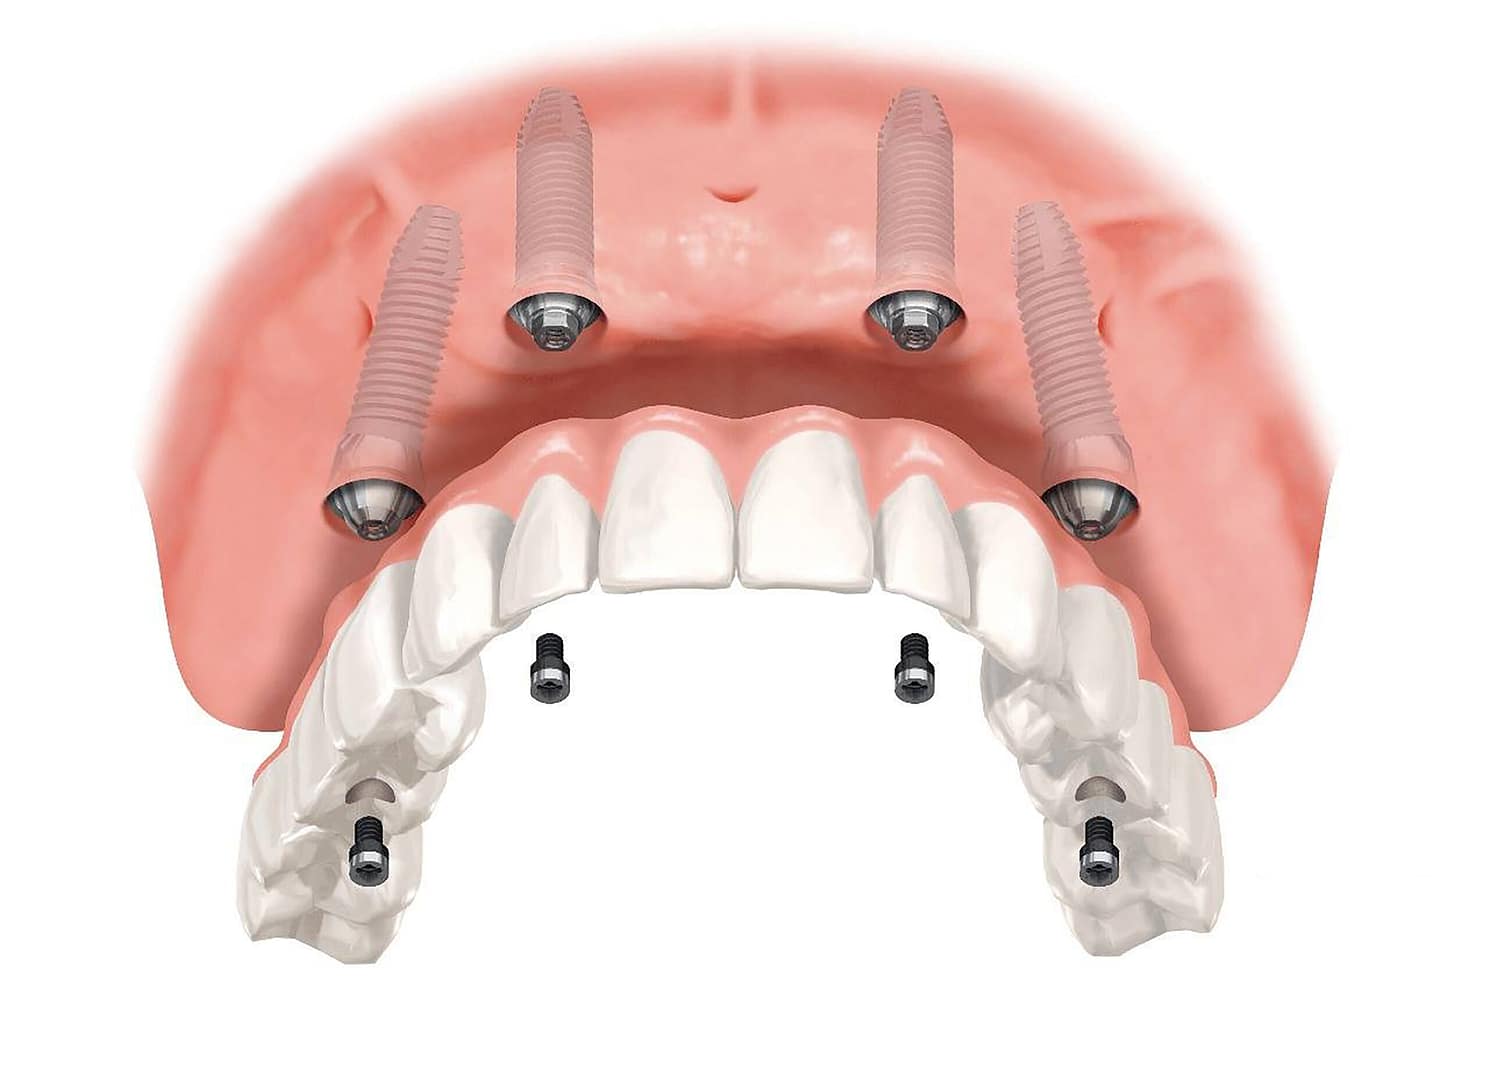

BlogEl Protocolo All-on-4®: Dientes Fijos y Función...

Leer másLun 17 de Nov – 2025